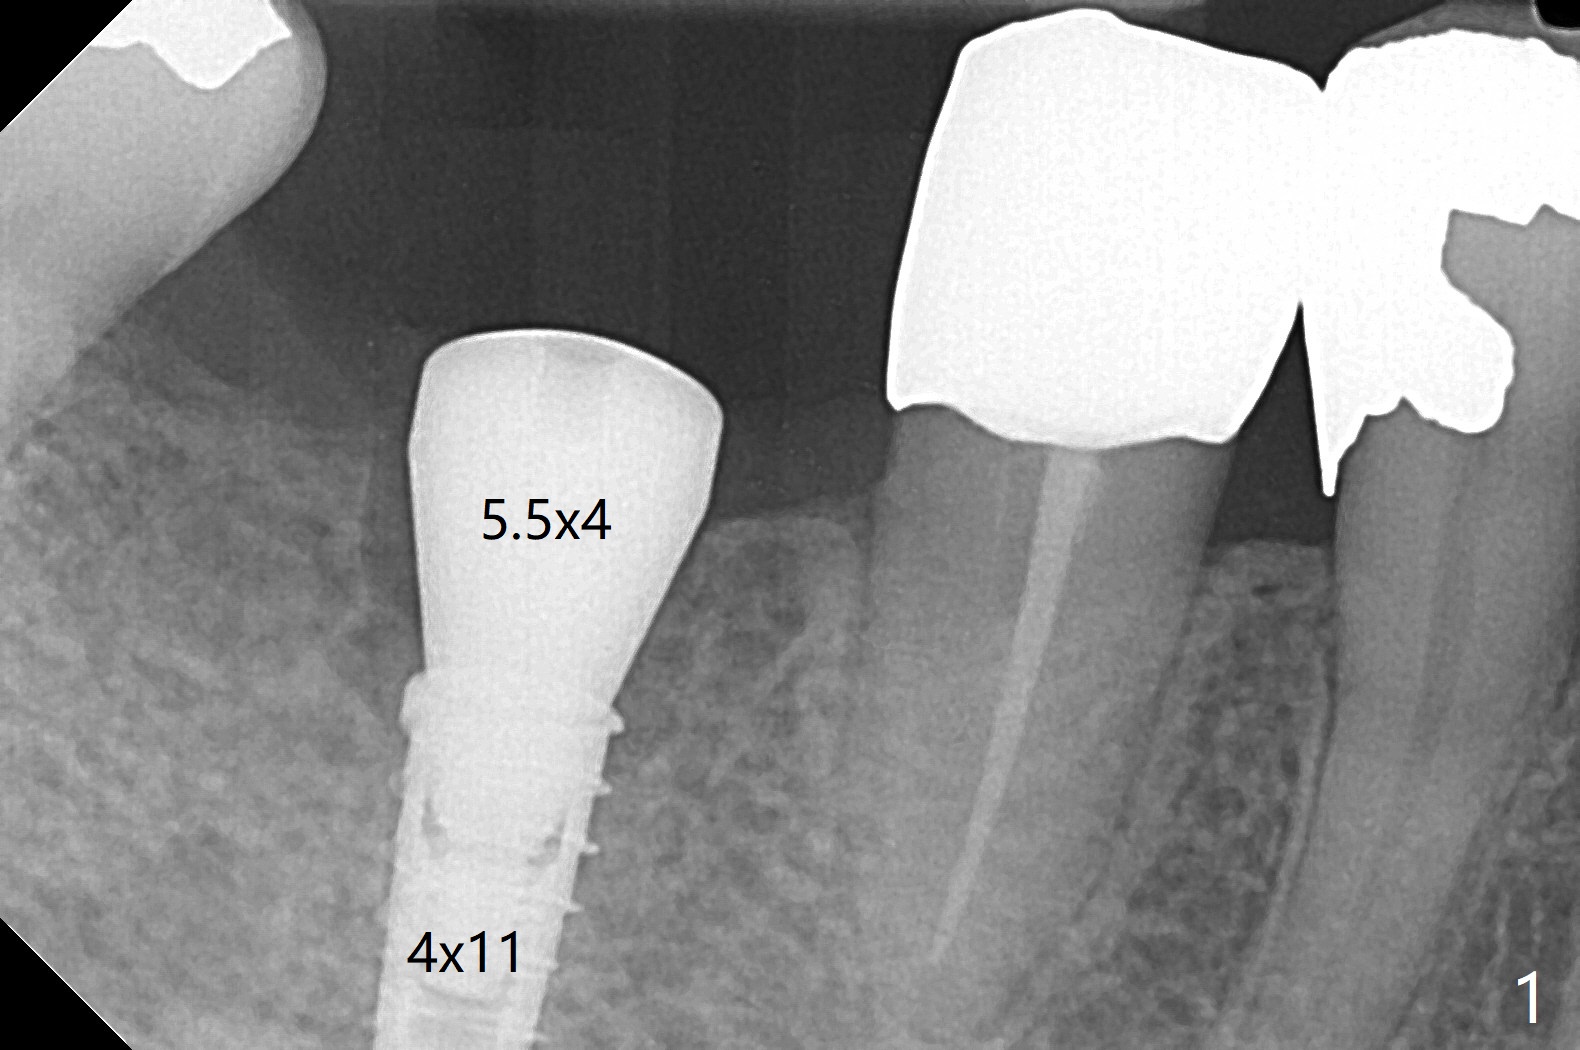

Since the preop ridge looks narrow at #30, incision is made, which makes it easy for observation of osteotomy. First, a 10.5 mm bone trimmer makes a deep dimple with apparently moderate ridge wide enough for a 4 mm implant. The patient has hypertension and cannot lie down for long. The bone density feels not high; a 4x11 mm (instead of 9 mm) implant is placed for 10 mm osteotomy (Fig.1 (~ 35 Ncm)). After use of 6 mm bone profile drill, there is bone buccal (less) and lingual to the implant. A 5.5x4 mm healing abutment is inserted, barely supragingival. As the implant is 1 mm longer than the design, regional panoramic X-ray is taken to determine clearance from the Inferior Alveolar Canal (Fig.2 red dashed line (the upper border). There is crestal bone loss 4 months postop (Fig.3,4). It appears that the implant was placed excessively deep. There is no implant thread exposure 9 months post cementation (Fig.5,6).